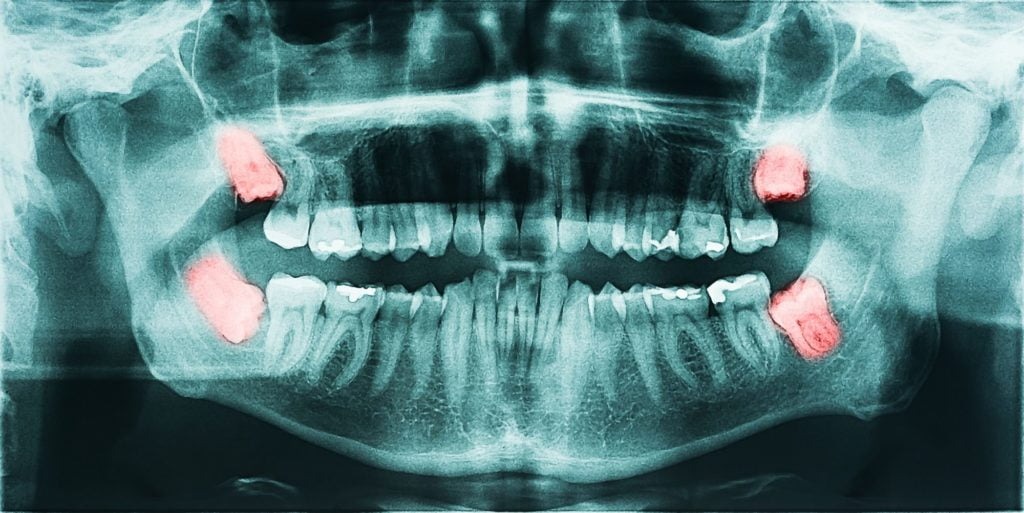

A panoramic dental X-ray is a fundamental component of modern dental diagnostics. Unlike traditional bitewing X-rays that focus on a small portion of your mouth, panoramic imaging offers a 360-degree view. This comprehensive scan allows dentists to:

- Detect impacted teeth or jaw disorders

- Assess bone structure for implants

- Identify signs of oral cancer or infections

- Monitor development in children and adolescents

- Evaluate issues not visible through regular exams

Because it captures so much information in one image, this scan helps in forming an accurate and complete treatment plan. Without it, you or your dentist might miss something critical that could change the course of treatment entirely.